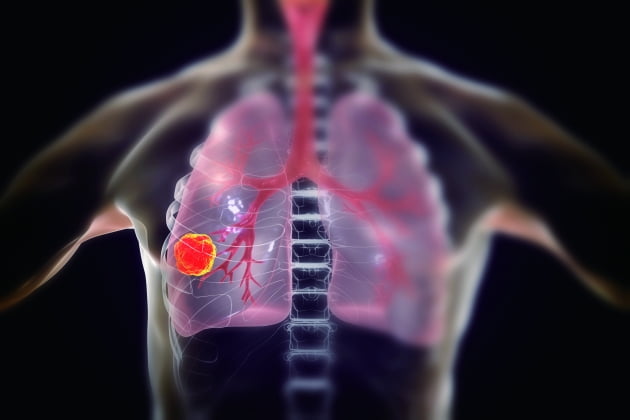

폐암 초기증상 및 원인

폐암 이란

폐암은 원발성 폐암을 말하며 원발성 폐암은 폐에서 기원하는 악성 종양을 말한다. 폐로 전이된 암은 폐로 전이된 것으로 분류되며, 폐암이라기 보다는 기원 장기로 전이된 것으로 분류된다. 폐암은 조직학적 유형에 따라 크게 소세포폐암과 비소세포폐암으로 분류된다.